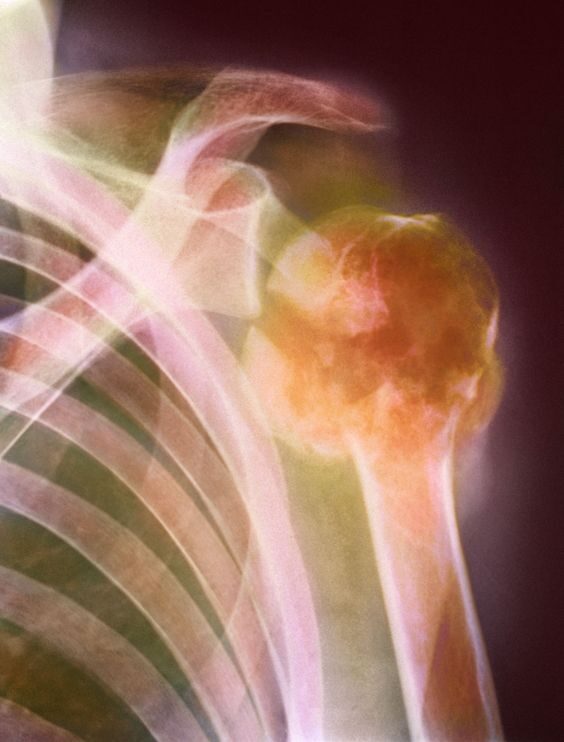

Va ricordato che l’età media di chi si ammala di mieloma multiplo è superiore ai 50 anni, anche se iniziano a registrarsi sempre più spesso casi nella popolazione sotto questa soglia di età. Le persone più a rischio restano gli anziani over 70, che lamentano fratture e generali difficoltà nei movimenti. Il mieloma multiplo, infatti, colpisce più gli uomini che le donne e tra i sintomi comuni annovera il dolore alle ossa, localizzato soprattutto a livello di schiena, anca e busto. La fragilità ossea comporta fratture anche in seguito a traumi lievi e si accompagna a una generalizzata anemia che causa forte stanchezza.